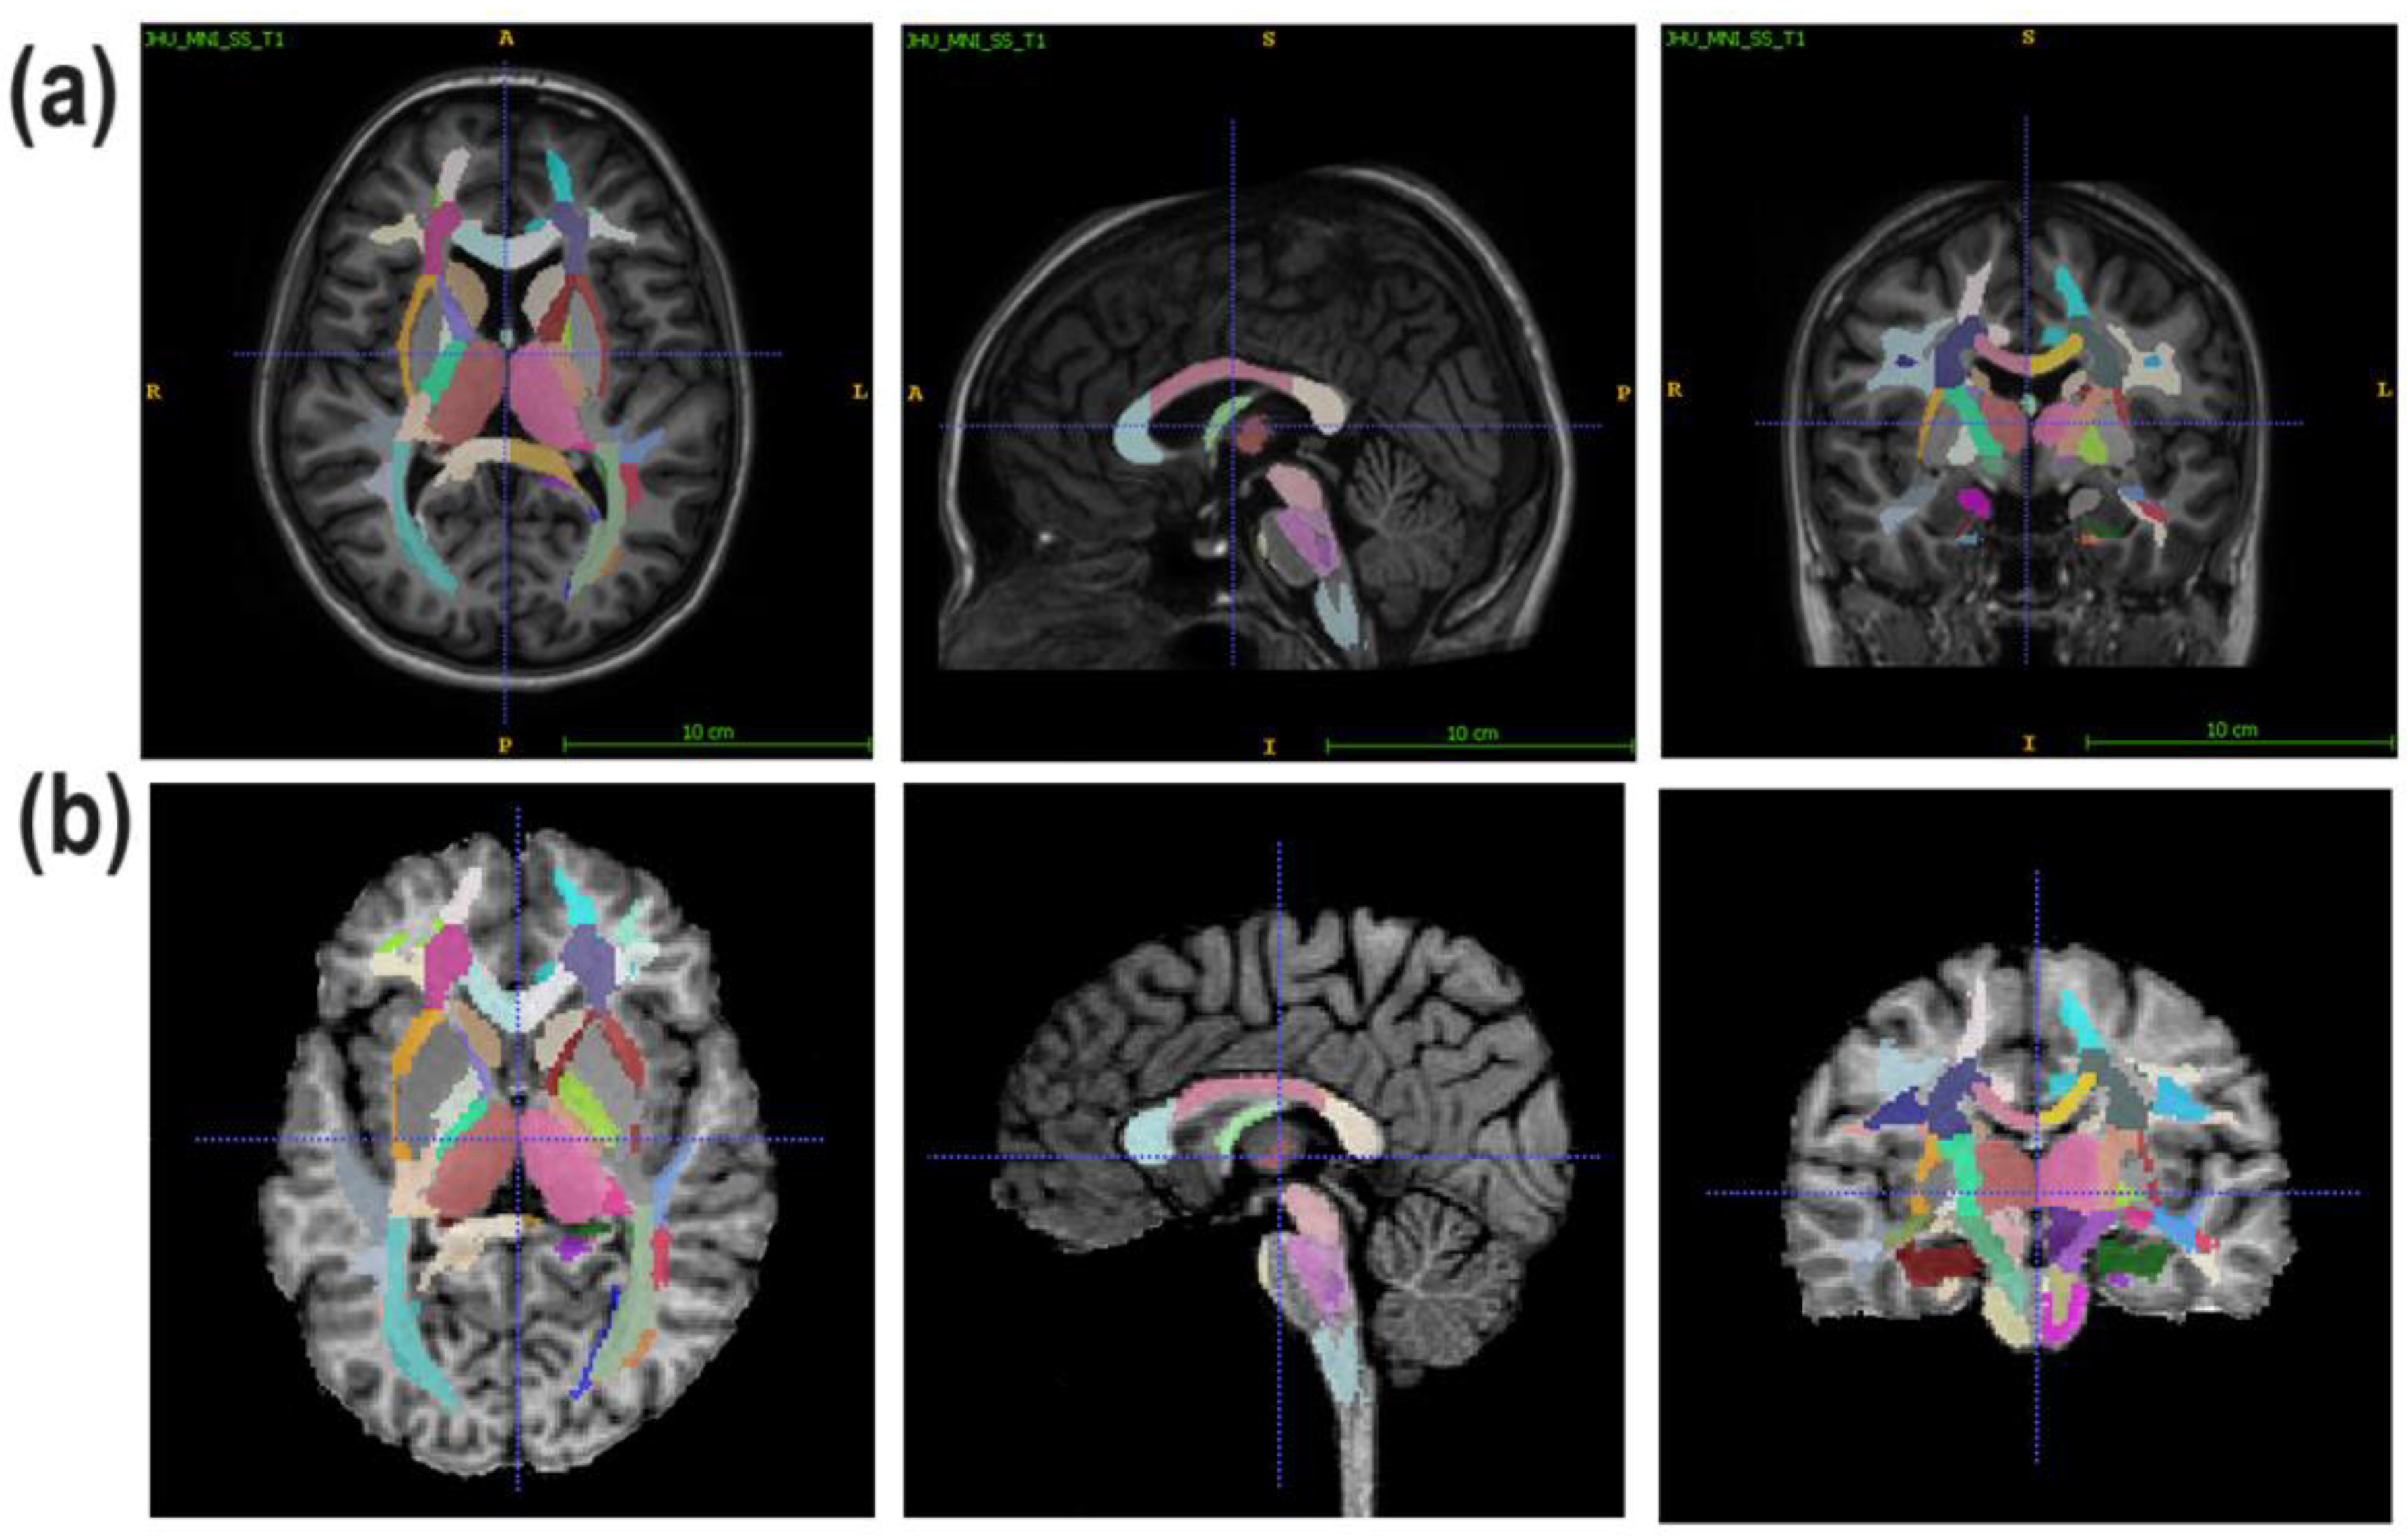

2.4. Image Processing

- Juxtacortical (superficial) WM: superior parietal, superior, middle, and inferior frontal; lateral and middle fronto-orbital; rectus; precentral; postcentral; angular; pre-cuneus; cuneus; lingual; fusiform; superior, inferior, and middle occipital; superior, inferior, and middle temporal; supramarginal; the cingulum (parts of the cingulate gyrus and hippocampus);

- WM pathways and fasciculi: corticospinal tract (CST); anterior, superior, and posterior corona radiata (CR); anterior limb, posterior limb, and retrolenticular part of internal capsule (IC); genu, body, and splenium of corpus callosum (CC); medial lemniscus; inferior, superior, and middle cerebellar peduncles (CPs); cerebral peduncles; posterior thalamic radiation; fornix (FX) (stria terminalis, column, and body); superior longitudinal (SL) fasciculus; superior (SFO) and inferior fronto-occipital (IFO) fasciculi; uncinate fasciculus; sagittal stratum; external capsule; pontine crossing tract; tapetum;

- Subcortical and allocortical GM structures: amygdala; caudate nucleus; putamen; globus pallidus; hippocampus; entorhinal area; thalamus;

- Brainstem structures: medulla; pons; midbrain.